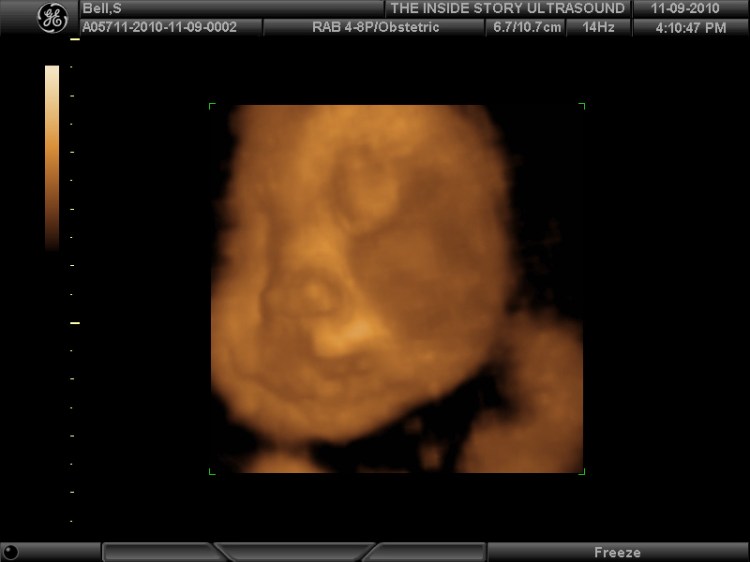

File:3D Ultrasound (5164126570).jpg - Wikimedia CommonsLos Ultrasonidos 4D son una tecnología de vanguardia que utiliza ondas sonoras para crear imágenes en tiempo real del feto. Estas imágenes permiten a los médicos ver el tamaño, la forma y el movimiento del feto, lo que les ayuda a determinar su crecimiento y desarrollo. Además, los Ultrasonidos 4D permiten a las madres tener una visión mucho más clara y detallada de su bebé en el vientre materno, lo que les permite establecer una conexión emocional más fuerte con él antes de su nacimiento.

Además de ser una experiencia emocionante y educativa, los Ultrasonidos 4D también tienen una importancia médica. La tecnología avanzada permite a los médicos detectar problemas de salud en el feto y en la madre de manera temprana, lo que les permite tratar estos problemas antes de que se conviertan en algo más graves. Esto no solo mejora la atención médica para el feto y la madre, sino que también aumenta las posibilidades de un embarazo exitoso y un nacimiento saludable.